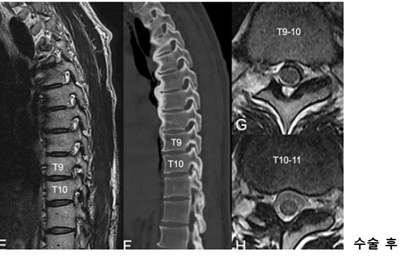

<»çÁø  ³»½Ã°æ ÈÄ¿ÜÃø Ãß°£°ø È®Àå¼ú »ç·Ê> °ú°Å °æÃß ÈıüºÇü¼ú°ú °³¹æÇü ÈäÃß µð½ºÅ©ÀýÁ¦¼úÀ» ¹ÞÀº ȯÀÚ, ÈäÃß 9~10¹ø°ú 10~11¹ø ºÎÀ§¿¡ Ãß°£°ø ÇùÂøÁõÀÌ ¹ß°ßµÅ ³»½Ã°æ ÈÄ¿ÜÃø Ãß°£°ø È®Àå¼ú·Î È£ÀüµÊ.

³í¹®¿¡ µû¸£¸é, ¼ö³â µ¿¾È µî ÅëÁõ, ¿·±¸¸® ÅëÁõ, ¾ûµ¢ÀÌ ÅëÁõ µîÀ» È£¼ÒÇÑ 3¸íÀÇ È¯ÀÚ¿¡°Ô¼­ ÈäÃß Ãß°£°ø ÇùÂøÁõÀ» ¹ß°ßÇß°í º¸Á¸¿ä¹ý¿¡µµ È£ÀüµÇÁö ¾Ê¾Æ ºÎºÐ¸¶Ãë ÇÏ¿¡¼­ ³»½Ã°æ È®Àå¼úÀ» ½ÃÇàÇß´Ù. °¢ ȯÀÚ´Â ¼ö¼ú Á÷ÈÄ ÅëÁõÀÌ ¿ÏÈ­µÇ¾úÀ¸¸ç ¸î ½Ã°£ µÚ º¸ÇàÀÌ °¡´ÉÇß°í ´çÀÏ Åð¿øÇÒ Á¤µµ·Î È£ÀüµÆ´Ù. 12~15°³¿ù µ¿¾ÈÀÇ ÃßÀû°üÂû¿¡µµ ¼ö¼ú ÈÄ ÇÕº´ÁõÀº ÀüÇô ¾ø¾úÀ¸¸ç, ½Ã°¢ÅëÁõÁ¡¼ö(VAS)¿¡¼­ °¢°¢ 8Á¡¿¡¼­ 0Á¡À¸·Î, 7Á¡¿¡¼­ 0Á¡À¸·Î, 6Á¡¿¡¼­ 1Á¡À¸·Î °³¼±µÆ´Ù.

ƯÈ÷ ÇÑ È¯ÀÚ´Â °ú°Å °æÃß ÈıüºÇü¼ú°ú °³¹æÇü ÈäÃß µð½ºÅ©ÀýÁ¦¼úÀ» ¹ÞÀº ÀÌ·ÂÀÌ ÀÖ¾úÁö¸¸ ÈÄ¿ÜÃø Á¢±ÙÀ» ÅëÇØ ³»½Ã°æ¸¸À¸·Î ¾ÈÀüÇÏ°Ô Ä¡·á°¡ µÇ¾úÀ¸¸ç, ¶Ç ´Ù¸¥ ȯÀÚ´Â °ñ´Ù°øÁõ¼º °ñÀýÀÌ ÀÖ¾úÁö¸¸ Àü½Å¸¶Ãë ¾øÀÌ ÃÖ¼Ò Àý°³·Î ¼º°øÀûÀ¸·Î Ä¡·áµÇ¾ú´Ù.